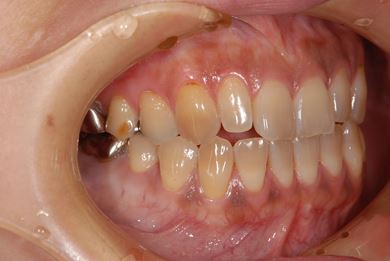

治療前

• 治療前